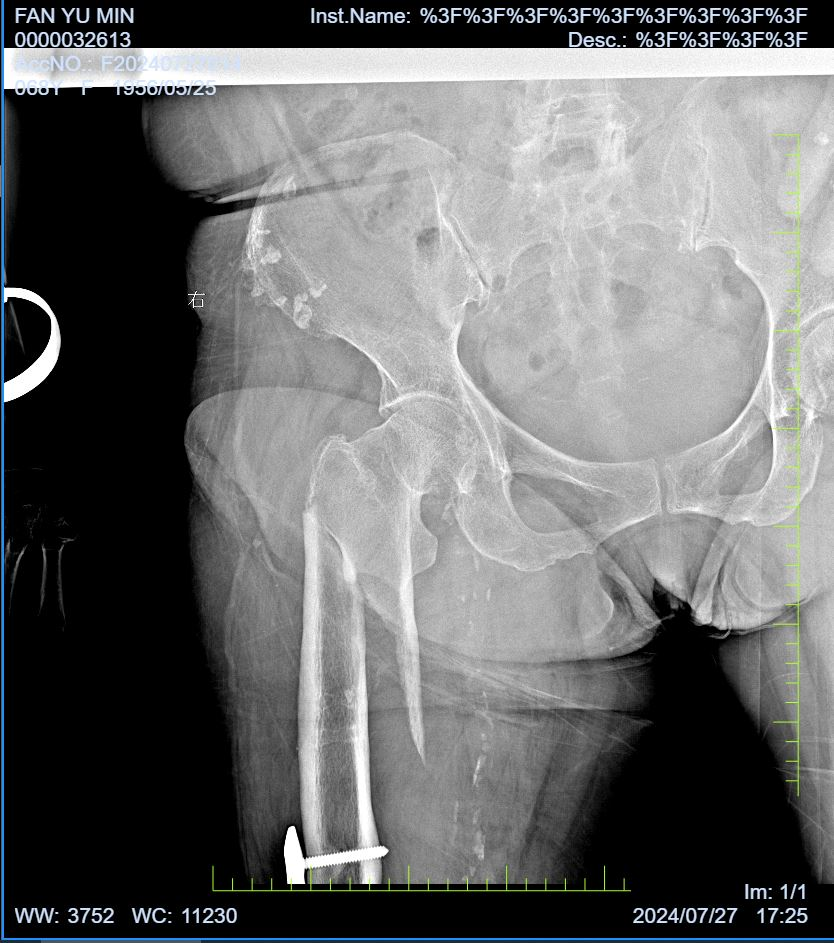

患者范奶奶今年70多岁了,因在家中不慎摔倒导致右侧大腿严重受伤,出现剧烈疼痛和外观畸形,活动受到限制,幸无皮肤破损及出血现象。伤后,范奶奶未出现头晕、头痛、心慌或气促等并发症,鉴于疼痛难忍,为求进一步治疗,她来到蚌埠市第四人民医院(市康复医院)骨科寻求帮助,经过门诊拍片后确诊为“右侧股骨干骨折”,随即安排入院治疗。

入院后,我院骨科团队迅速为范奶奶完善了相关检查,建议其卧床休息,同时采取抗炎止痛、患肢抬高牵引制动等综合治疗措施。值得注意的是,范奶奶右侧股骨有多次骨折病史,并接受过多次手术治疗。目前,她上次右侧股骨下段骨折的内固定装置尚未取出。针对这一复杂情况,我院骨科联合手术室(麻醉科)、护理部等多学科专家,对范奶奶的病情进行了全面而细致的评估与研讨,共同制定了周密的麻醉及手术方案。